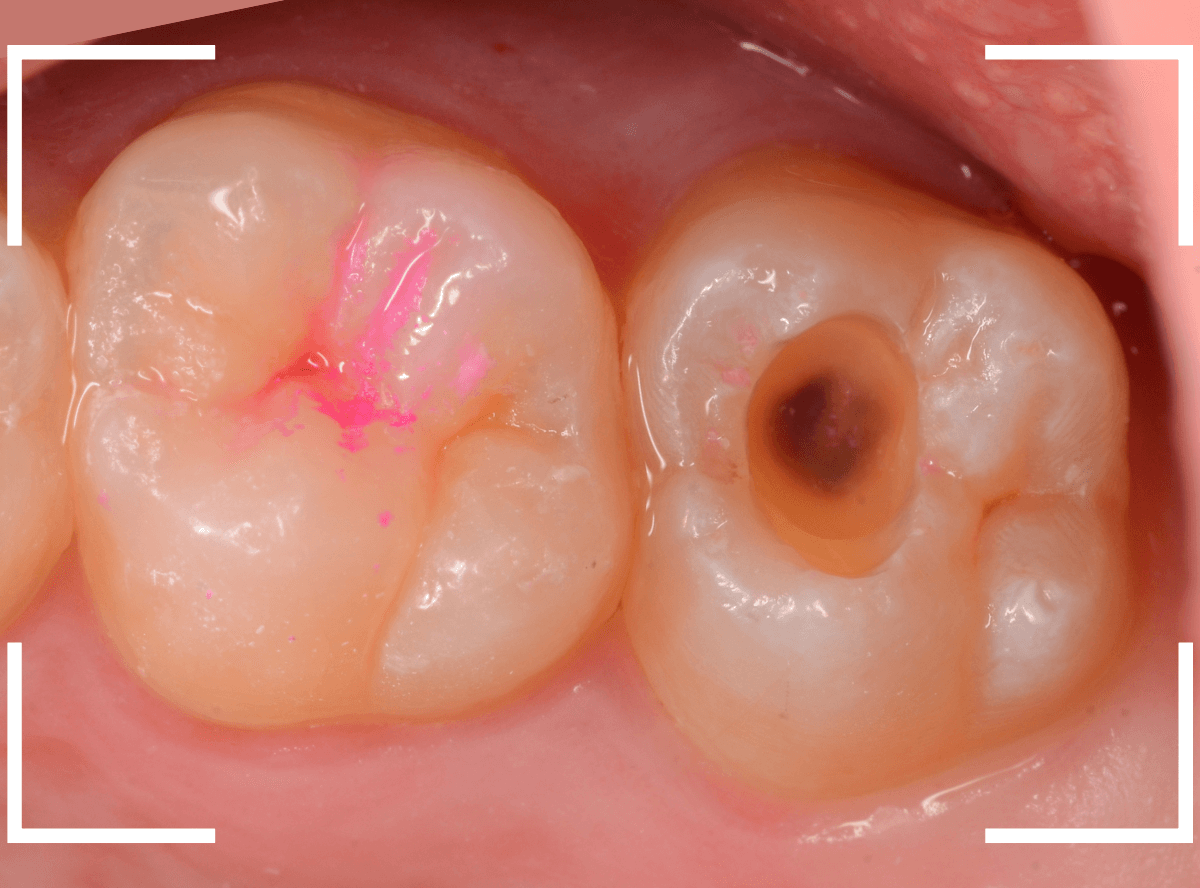

写真では、2本の歯とも、歯の溝に虫歯が出来ているのが確認できます。

レントゲン写真で確認します。

〇部が虫歯の部分です。

左側の歯はうっすらと黒い影が見えますが、わかりづらい写り方です。

虫歯の部分を少しずつ削りながら、虫歯を確認します。

左側の歯はかなり虫歯が広がっているのがわかりますね。

典型的な、内部で広がる小窩裂溝う蝕です。